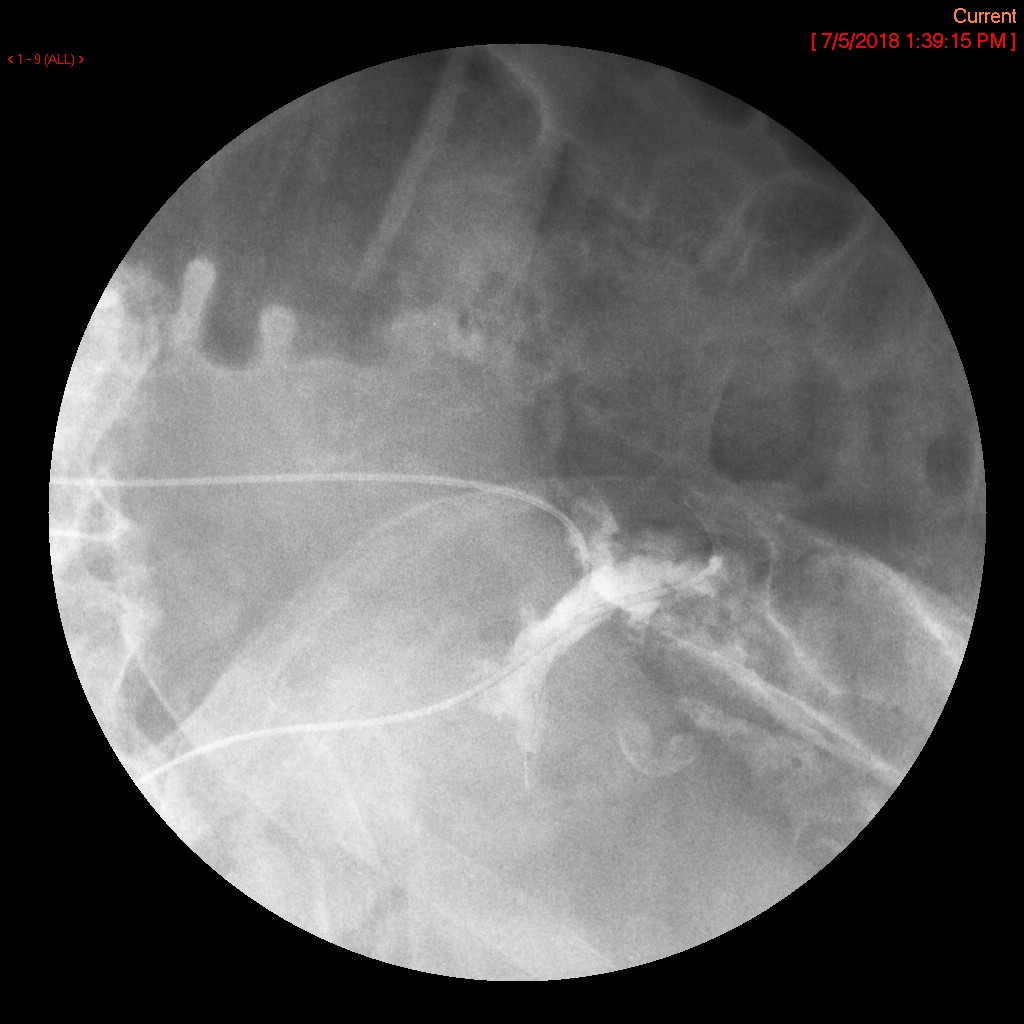

- The gynecologist will begin injecting contrast material into the uterus. Obtain images periodically throughout the procedure (usually at the direction of the gynecologist). The images should include the uterine cavity filled with contrast material, bilateral fallopian tubes filled with contrast material, and spillage and dispersion of contrast material into the peritoneal cavity (image 1) (image 2) (image 3) (image 4) (image 5).